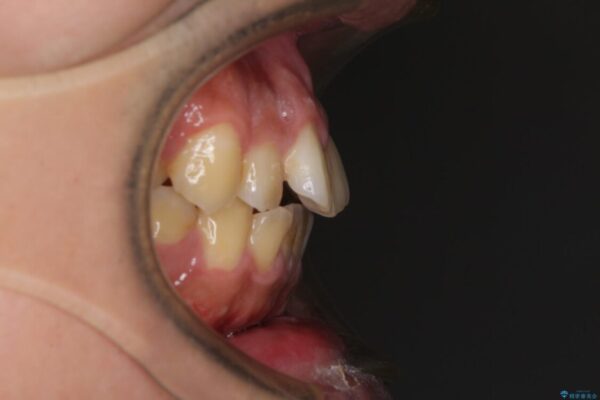

治療前

• 後戻りでデコボコの前歯 インビザライン矯正治療 治療前画像